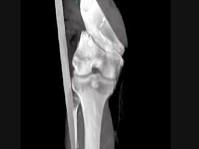

问题 男,45岁,车祸后左膝部剧痛,活动受限2小时,结合影像学检查,最可能的诊断是?(?)

选项 A.股骨颈骨折 B.股骨下端骨折 C.柯莱斯骨折 D.胫骨骨折 E.腓骨骨折

答案 B